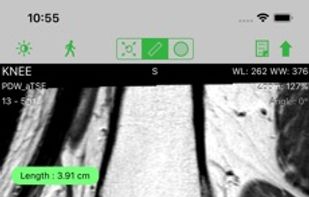

DICOM viewer. RadiAnt is a DICOM viewer for medical images designed to provide you with a unique experience. With its intuitive interface and unrivaled performance, you'll never look back.